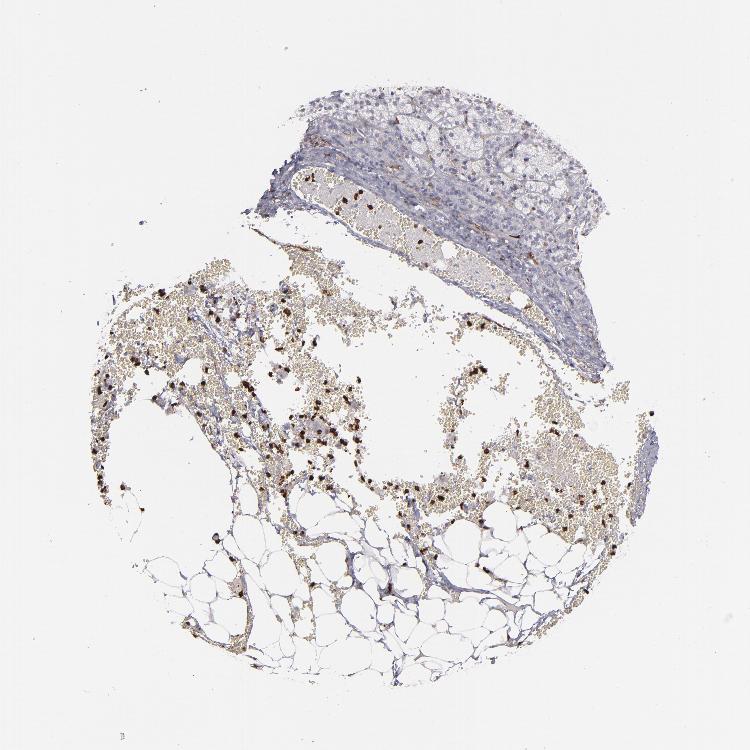

ADRENAL GLAND - Antibody stainingi

Antibody staining in the annotated cell types in the current human tissue is reported as not detected, low, medium, or high, based on conventional immunohistochemistry profiling in selected tissues. This score is based on the combination of the staining intensity and fraction of stained cells.

Each image is clickable and will lead to virtual microscopy that enables deeper exploration of all samples and also displays staining intensity scores, fraction scores and subcellular localization as well as patient and tissue information for each sample.

Antibody HPA002327Antibody HPA006040Antibody CAB022160

Glandular cells Not detectedNot detectedNot detected